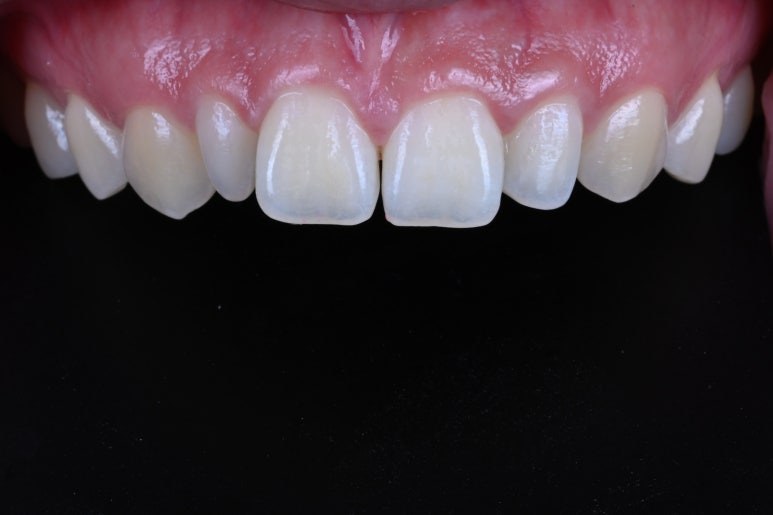

살짝 치아를 다듬어드리고 난 뒤의 사진입니다.

대부분 앞면만 매끈하고 부드럽게 다듬어드렸어요.

또한!!! 잇몸 성형도 함께 해드려서 최대한 대칭으로, 이상적인 라미네이트 형태가 될 수 있도록 기획!